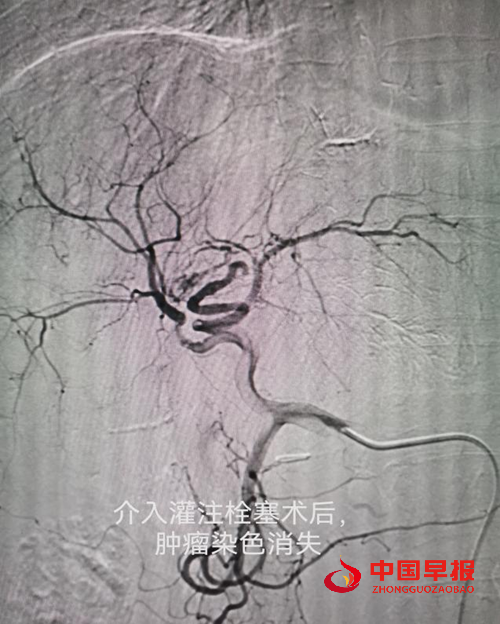

本门诊的核心特色在于融合了两大前沿技术:细胞与基因技术和介入微创技术。这一创新组合打破了细胞传统治疗的局限,结合介入技术,创新细胞精准递送方式,能够快速、高效、均衡将细胞灌注到肿瘤或者靶器官,实行更精确、更高效、无副作用治疗,同时针对疾病的根本病因,为每位患者量身定制“一对一”的个体化治疗策略,实现真正意义上的精准医疗。

车能雨教授病例展示:

病例一:刘先生,男,55岁,患肺癌,经过三次介入微创手术+三次细胞治疗+靶向治疗,肺癌缩小90%,全身脊柱转移灶得到控制硬化,全身剧痛消失,处于NED状态。

病例二:李女士,52岁,患胆管癌,经过一次介入微创治疗+三次细胞治疗+靶向治疗,胆管癌大部分消失,临床症状大部分好转,暂处于NED状态。